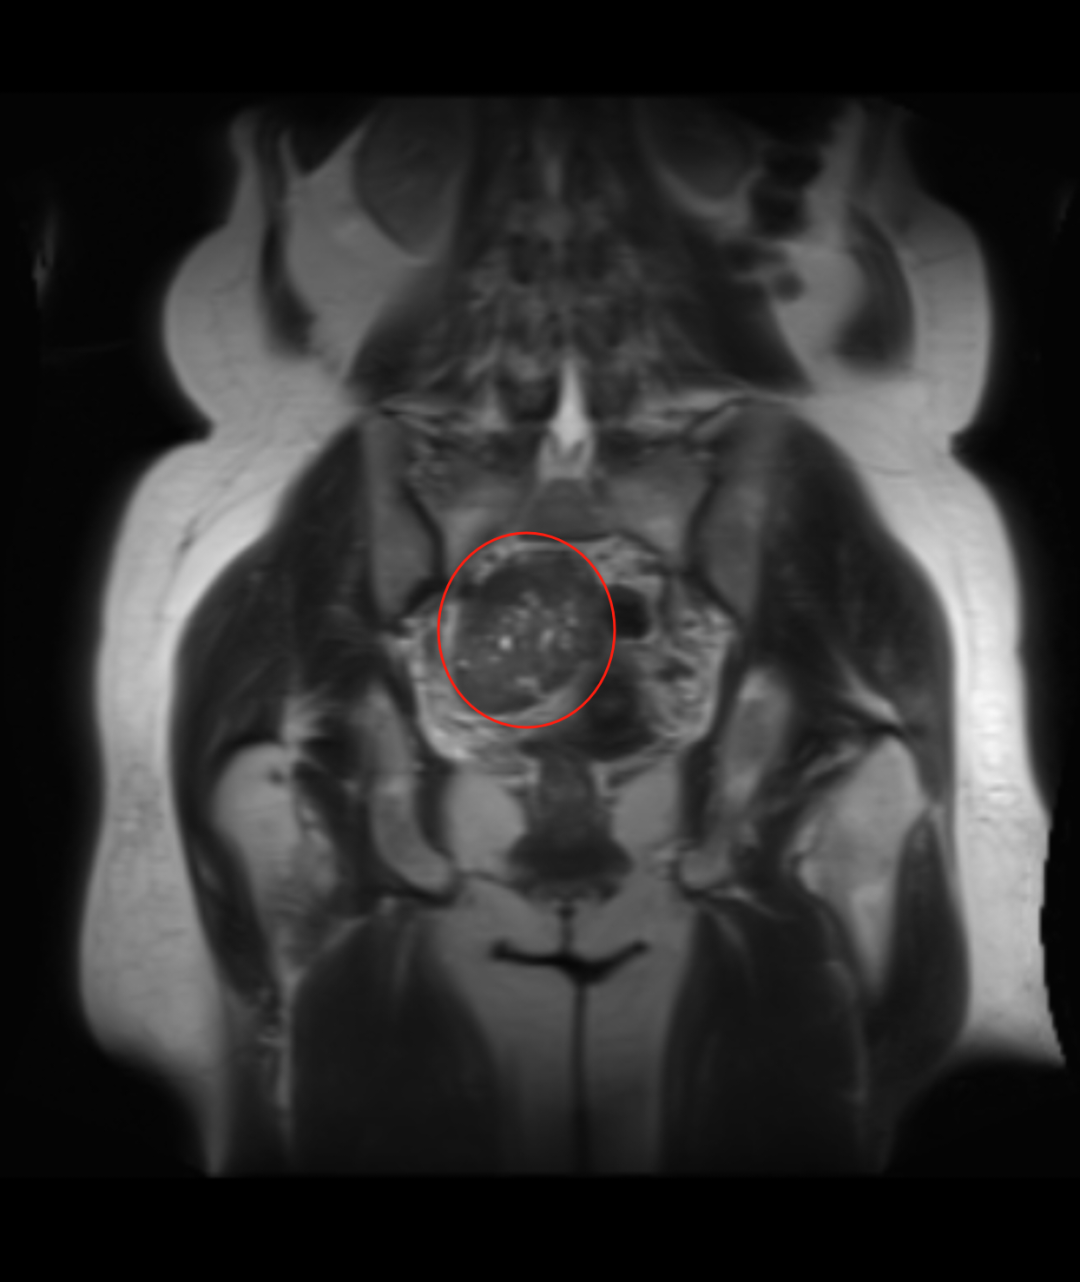

入院后,妇科团队为戴阿姨完善了盆腔增强MRI、肿瘤标志物、性激素六项等相关检查。结合影像学特征和实验室结果,初步诊断为“子宫阔韧带良性肌瘤”。徐彩临院长带领妇科医护团队立即展开病例讨论:患者53岁,处于围绝经期,肌瘤体积较大(直径超10cm),虽考虑良性,但已可能压迫周围脏器,且存在潜在生长风险,符合手术指征。腹腔镜微创手术具有切口小、出血少、术后恢复快等优势,最终确定腹腔镜下右侧阔韧带肌瘤剔除术为首选方案,但手术难度大。